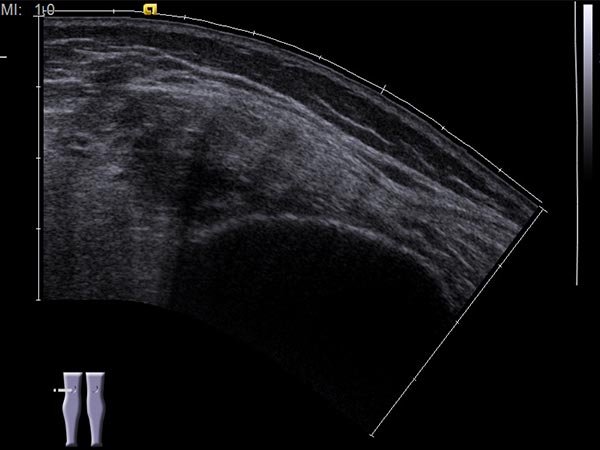

Ultraschallbild (automatisch zusammengesetzte 2D-Darstellung) vor Sklerotherapie. Die hier dargestellten, initial noch echoärmeren Hohlräume der venösen Malformation werden durch die Inflammation, die durch die Sklerosierungstherapie induziert wird, verschlossen werden.